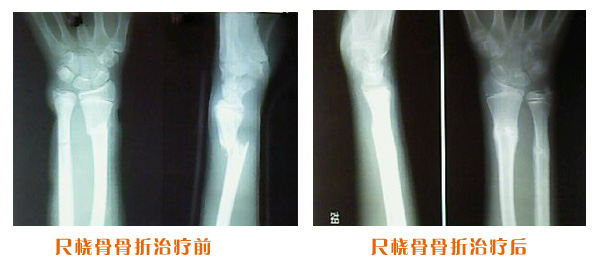

肥城市安駕莊梁氏骨科醫院是一所以梁氏手法正骨配合膏藥為特色的現代化專科醫院。

梁氏骨科術始創于清雍正年間,歷經八代,至今已有三百年歷史。據1929年泰安縣志載“梁瑞圖先生,字增生,號蓮峰,安駕莊人,精岐黃并發明接骨,凡跌打車凡跌打車軋皮不破而碎骨者......【詳細】 |